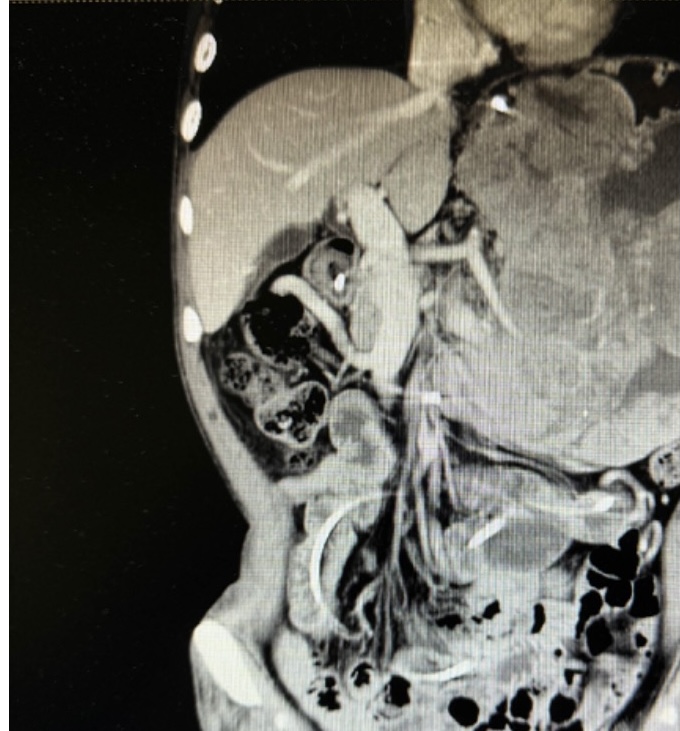

患者术前影像资料

张翼主任医师接诊后,第一时间牵头对患者进行全面评估,经影像检查进一步确认:肿瘤体积巨大且与脾动脉粘连紧密,术中稍有不慎就可能引发致命性大出血,手术难度远超常规胃肠肿瘤手术。为最大程度降低风险,张翼教授先后多次组织全院大会诊,联合麻醉科、输血科、重症医学科、影像医学科等多学科专家反复推演手术方案,从手术入路的选择、血管保护的细节,到术中输血预案、术后并发症防控,每一个环节都制定了详尽的应对策略。